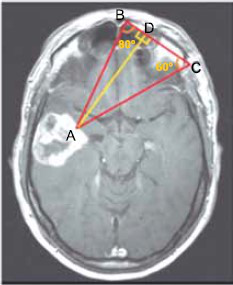

A imagem, obtida por tomografia computadorizada, revela a presença de um tumor cerebral no ponto A. O método de triangulação sobre essa imagem indica que as medidas dos ângulos A!$ \widehat{B} !$C e A!$ \widehat{C} !$B são, respectivamente, 80° e 60°.

(https://drbraindrop.wordpress.com)

Adotando-se tg 60º = m, tg 80º = n e utilizando-se a medida !$ \overline{BC} !$ de igual a !$ \mathcal{l} !$, a distância do ponto A ao segmento de reta !$ \overline{BC} !$ , indicada na figura por !$ \overline{AD} !$ , será igual a